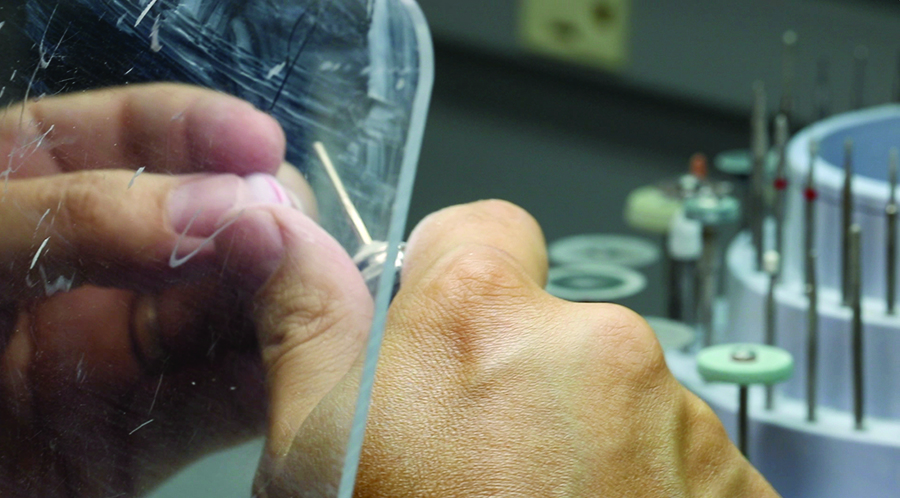

The scanned model for planning the restoration in inLab.

Fig. 13B

Design of crowns and veneers in inLab.

Fig. 13C

Marking the preparation margin for designing a crown in inLab.

Fig. 14A

The CAD/CAM manufactured veneers and crowns for individualization on the maxillary model.

Fig. 14B

The CAD/CAM manufactured veneers and crowns for individualization on the maxillary model.

Fig. 14C

The CAD/CAM manufactured veneers and crowns for individualization on the maxillary model.

Fig. 14D

The CAD/CAM manufactured veneers and crowns for individualization on the maxillary model.